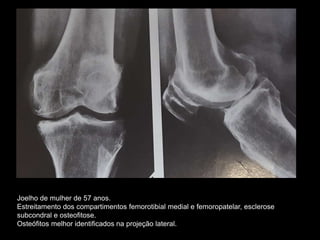

Joelho de mulher de 57 anos.

Estreitamento dos compartimentos femorotibial medial e femoropatelar, esclerose

subcondral e osteofitose.

Osteófitos melhor identificados na projeção lateral.